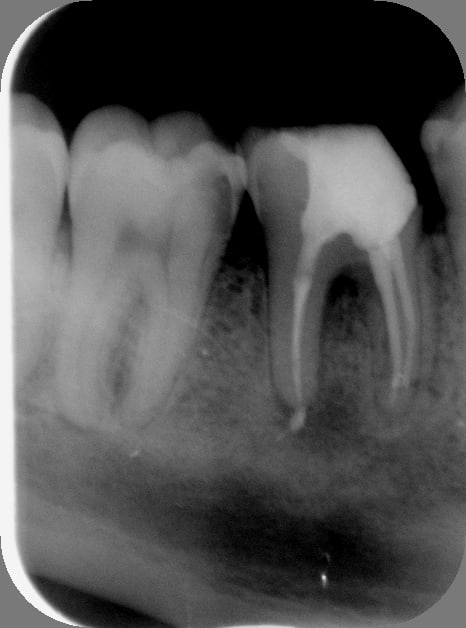

Les canaux mésiaux sont obturés, c'est dommage, mais ça ne change pas grand chose dans le cas présent. Le pire à reprendre c'est le distal car obturé à l'apex, mais c'est pas un drame non plus.

On me demande souvent quel est le pourcentage de chance pour que ça guérisse. Il y aurait environ vingt pour cent d'échecs sur les repises de traitements avec foyers infectieux, quand réalisés dans les règles de l'art.

Mais dans le cas présent je dirais à la vue de la rétro que le pronostic d'un retraitement devrait être bon.

Donc dans ton cas le problème se situe surtout au niveau mésial,et ta cavité d'accès est insuffisante pour cathétèriser

Si tu étais parvenu à désinfecter et obturer effectivement à 1mm de l'apex radio il est conseillé une obturation étanche

pour ne pas prendre de risque d'essaimage bactérien.Si tu le faisais après ton traitement,les risques de reprises infectieuses sont très grand,puisqu'une image de LA au départ.

Seul un endo exclusif sous micro peut reprendre ton endo qui s'est transformé en RTE.